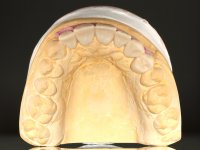

O paciente foi observado conjuntamente e a dúvida que surgiu de imediato foi se seria possível com a regeneração óssea a efectuar poder ser reabilitada naturalmente a zona das papilas interdentárias. Nesse sentido foi feito um enceramento de diagnóstico que contemplaria as duas hipóteses, utilizando ou não a cerâmica gengival. A confecção desse enceramento foi fundamental para expor ao paciente a dificuldade da reabilitação. O wax-up deu origem a um mock-up que foi aprovado pelo paciente e que simultaneamente serviu de guia imagiológica. O caso foi planificado cirurgicamente e realizada uma guia cirúrgica com que foram colocados os implantes. Após 10 semanas foi feita a 1ª impressão para confecção da ponte provisória. Foram criados os primeiros perfis de emergência na gengiva artificial e foi digitalizado o modelo. Por processo de CAD-CAM foi confeccionada uma ponte provisória aparafusada baseada no enceramento de diagnóstico. A ponte trabalhou durante 8 semanas os tecidos moles que foram fielmente copiados numa impressão com técnica de moldeira aberta. Os transferes foram individualizados com resina composta para copiarem fielmente os perfis de emergência criados pela ponte provisória. Confeccionado o modelo de trabalho definitivo, foi realizada uma infra-estrutura em zircónio seguindo a orientação do enceramento de diagnóstico. O assentamento da infra-estrutura foi testado em boca e simultaneamente foi novamente impressionados os tecidos moles com um silicone fluido. Nessa consulta foi feito o levantamento da cor. Os dentes 13 e 23 apresentavam uma saturação anormalmente forte que resolvemos não valorizar, optando por privilegiar a relação com o sector antero-inferior. Foi realizada uma nova gengiva artificial com a impressão que acompanhou a impressão de arrasto com a infra-estrutura. Após a colocação da cerâmica na infra-estrutura foram coladas as meso-estruturas. O trabalho final foi aparafusado lentamente permitindo a adaptação dos tecidos moles.